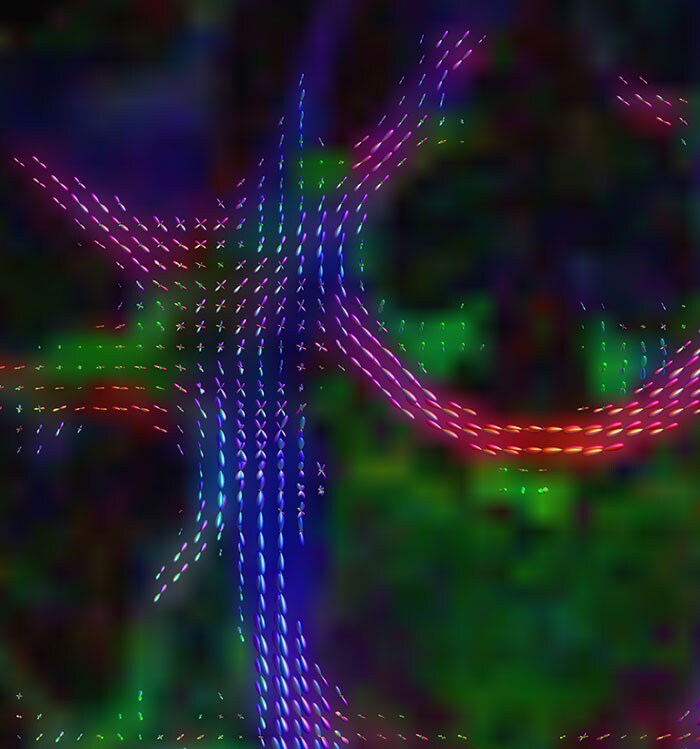

Simultaneous acquisition of multiple slices to accelerate fMRI and dMRI in the brain. A phase shift between slices is used to facilitate SENSE unfolding for obtaining the individual images.

These images are produced using the ABCD protocol and illustrate the use of more sophisticated and accurate models of diffusion. The color FA maps are shown for reference. The diffusion tensor model represents the diffusion within each voxel as an ellipsoid.

Alternative models, such as constrained spherical deconvolution, better capture the rich information available with the use of high b-value dMRI and many sampling directions. In much of the brain, voxels contain multiple white matter tracts, and it is essential to capture this information to be able to perform accurate tractography and generate diffusion connectomes.

Diffusion acquisition on Achieva 3.0T dStream with matrix 140x141, 81 slices, FOV 240x240 mm, voxels 1.7x1.7x1.7 mm, TR 5300 ms, TE 89 ms, flip angle 78, MultiBand SENSE factor 3, partial Fourier 0.645, 102 diffusion directions, b-values 0 (6), 500 (6), 1000 (15), 2000 (15), 3000 (60) , scan time 2x 4:37 min. Images provided by Dr. Watts.